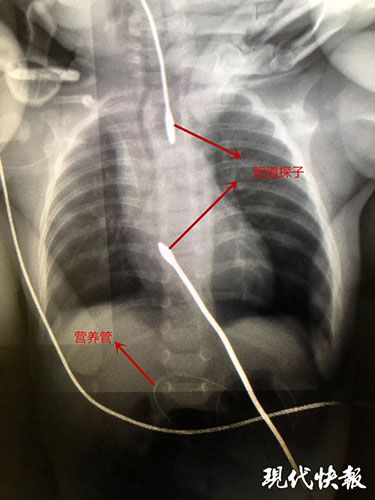

担心三次手术婴儿的身体扛不住 , 小儿外科主任李炳带队制定了稳妥的三次手术方案 。 “第一次是做胃造口 , 就是把胃提到腹壁上打个洞 , 主要目的一是用胆道探子做个张力延长 , 把两个盲端往中间牵拉重叠 , 到一定程度后再做第二次食管成形术 , 二是放入空肠营养管 , 第三次手术是关闭胃造口” 。

12月9日 , 手术团队为天天实施了第一次手术 , “第一次手术后最关键的外科治疗是胆道探子的张力性延长 , 力度要恰到好处 , 力道稍微大一些就会顶破食管 。 ”第一次手术很成功 , 在放入胆道探子的同时 , 医生在胃造口处放入了一根营养管 , 营养管直通天天小肠 , 未来数月天天就要靠这根管子维持营养 。